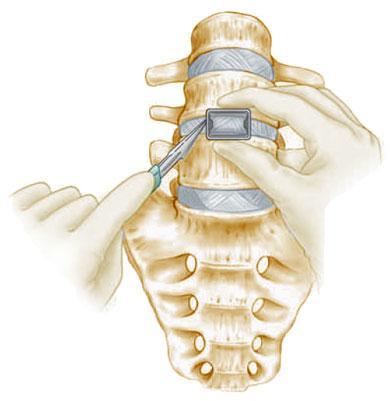

What is Vertebroplasty?Vertebroplasty is a minimally invasive spine procedure used to treat painful vertebral compressionfractures, most commonly caused by osteoporosis, trauma, or spinal tumors. In this procedure, aspecial medical bone cement is injected into the fractured vertebra to stabilize the bone andrelieve pain.The procedure is performed using image-guided techniques such as fluoroscopic X-ray guidance,allowing precise placement of the cement into the vertebral body. Vertebroplasty is widely usedto provide rapid pain relief and restore spinal stability in patients with compression fractures.SEO Keywords: Vertebroplasty Treatment, Spine Compression Fracture Treatment, MinimallyInvasive Spine Procedure, Spine SpecialistConditions Treated with VertebroplastyVertebroplasty is commonly recommended for patients with:• Osteoporotic vertebral compression fractures• Painful spinal fractures not responding to conservative treatment• Vertebral fractures due to trauma• Pathological fractures caused by tumors or metastasis• Persistent back pain due to vertebral collapseThis procedure helps stabilize the fractured vertebra and reduce severe back pain.1. The patient is positioned carefully on the operating table.2. A small needle is inserted into the fractured vertebra through the skin.3. Using real-time fluoroscopic X-ray guidance, the surgeon advances the needle into thevertebral body.4. A special bone cement is injected into the fractured vertebra.5. The cement hardens quickly, stabilizing the bone and relieving pain.The entire procedure is minimally invasive and typically requires only a small skin puncture.Advantages of VertebroplastyVertebroplasty offers several important benefits:• Rapid relief from severe back pain• Stabilization of the fractured vertebra• Minimally invasive procedure with very small incision• Short hospital stay• Faster recovery compared to open spine surgeryMany patients experience significant pain relief within 24–48 hours after the procedure.Role of X-Ray and ImagingImaging plays a critical role in vertebroplasty procedures.• X-rays and MRI scans help identify vertebral compression fractures and assess fracture severity.• Fluoroscopic real-time X-ray guidance ensures accurate needle placement during cementinjection.• Post-procedure X-ray radiographs confirm proper distribution of bone cement within thevertebral body.These imaging techniques ensure precision and safety during the procedure.Recovery After VertebroplastyRecovery after vertebroplasty is usually very quick compared to traditional spine surgery.Most patients can:• Walk within a few hours after the procedure• Return home on the same day or the next day• Resume light daily activities within a few days• Gradually return to normal activities with guided physiotherapyRehabilitation focuses on strengthening spinal muscles and preventing future fractures, especiallyin patients with osteoporosis.